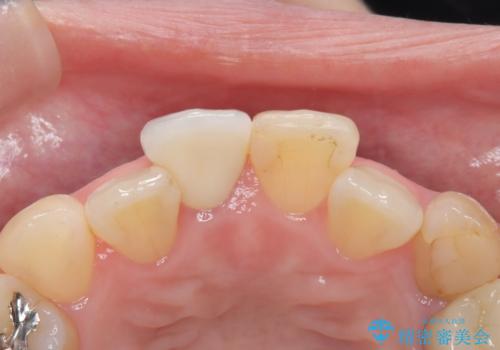

【オールセラミック】前歯の色を変えたい。

- 前歯の色が変色してきたことを主訴に来院されました。

根管治療から被せものまで治療を行いました。

オールセラミックは、透明感があり綺麗な色調を再現できます。